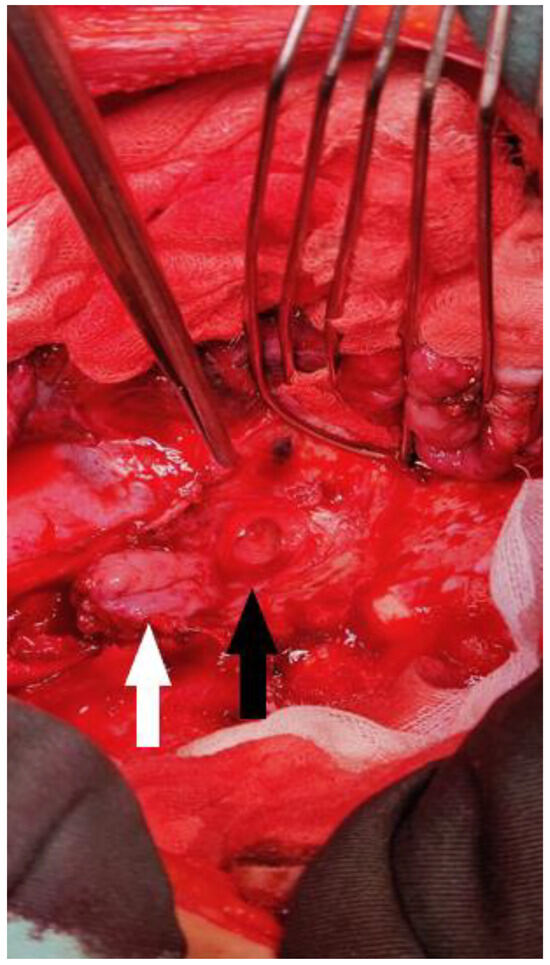

After the resolution of pneumonia, we evaluated the patient. Due to the size and localization of the fistula, no conservative management was possible, and we decided to move forward with the surgical repair of the fistula. Surgery was performed via a right posterolateral thoracotomy, and the gastric tube was disconnected from the esophagus, exposing a defect on the left main bronchus that was 18 mm in diameter. At this time, the patient was very thin; thus, there was no possibility of using the intercostal muscle flap to cover the defect. We decided on the only possible solution: using the posterior wall of the esophagus, proximal to the anastomosis. The esophagus was transected in such a manner that a posterior mucosal flap was created, which was 4 cm long and received a blood supply coming from the posterior esophageal wall (Figure 3). The flap was well vascularized and long enough. We covered the defect with the flap using absorbable 4.0 sutures. An air leak test was performed, showing no leak from the repaired fistula. The procedure was finished with a left cervicotomy and esophagostomy, as well as a median laparotomy and gastrostomy, which were performed on the partially resected gastric tube previously repositioned into the abdomen.

Figure 3.

Intraoperative image showing a defect on the left main bronchus (black arrow) and the esophageal flap prepared for suturing (white arrow). This image was taken after the gastric tube had been disconnected and the esophageal flap prepared. The surrounding tissue was fibrotic. The esophageal flap was well vascularized and had sufficient length.